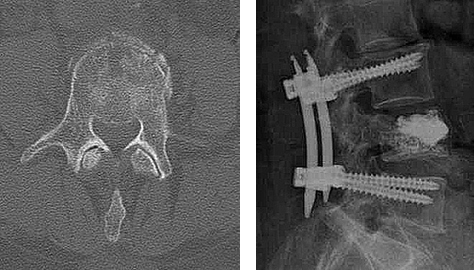

Minimalinvasive Stabilisierung eines Knochenbruchs an der Wirbelsäule von vorne

Nach Einrichtung eines komplizierten Bruchs wird mit Hilfe einer Haltevorrichtung der Weg zur vorderen Wirbelsäule freigehalten. Dadurch kann über einen sehr kleinen Schnitt eine Stabiliserung der vorderen Wirbelsäule erfolgen. Die postoperative Mobilisation erfolgt direkt nach der Operation ohne Korsett.